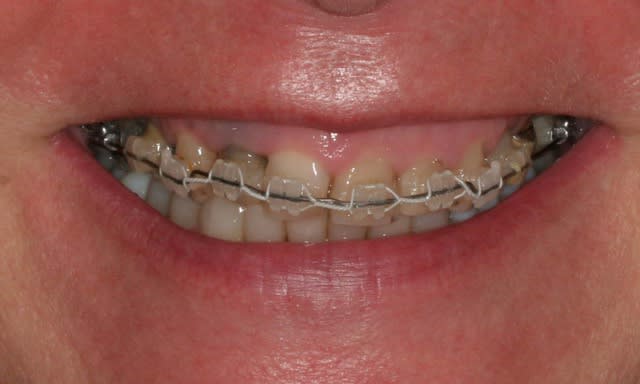

Récemment Céramik râlé, parce qu'il n'y avait pas de nouveau cas (esthétique je crois) à se mettre sous la dent. Je me jettes à l'eau avec ce dernier cas posé ce vendredi (y'a pas plus frais), une larme à l'oeil parce qu'il s'agit aussi du dernier gros cas dans mon cabinet que je quitte cette semaine pour rejoindre ma belle et nos p'tits bouts loin la bas dans le sud.

La patiente a un sourire très médiocre avec migration de plus en plus marqué du bloc incisivocanin sup. Comment l'aidez vous?